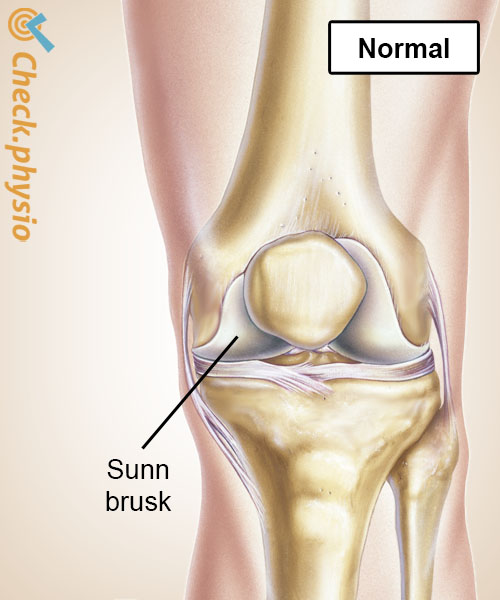

Leddflatene i knoklene er dekket av et tynt lag med brusk. Dette virker støtdempende og sørger for at knoklene i et ledd glir lett over hverandre. Ved artrose reduseres brusken i kvalitet. Dette gjør at leddet beveger seg mindre smidig, og støtene dempes dårligere.